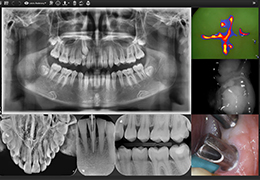

View X-Ray CT & MRI Scans Fast and Easily

Designed for surgeons, Pro Surgical 3D makes it easy to view patient scans quickly. Pro Surgical 3D facilitates the optimal 3D treatment and assessment workflows based on X-ray CT and MRI scans – and best of all, it’s FREE!

Traditional multi-planar slicing

High-quality and fast 3D reconstruction and 3D rendering

Performs 3D reconstruction and volume rendering.

Multi-planar slicing.

Side-by-side comparative assessment for pre- and post-operative scans.